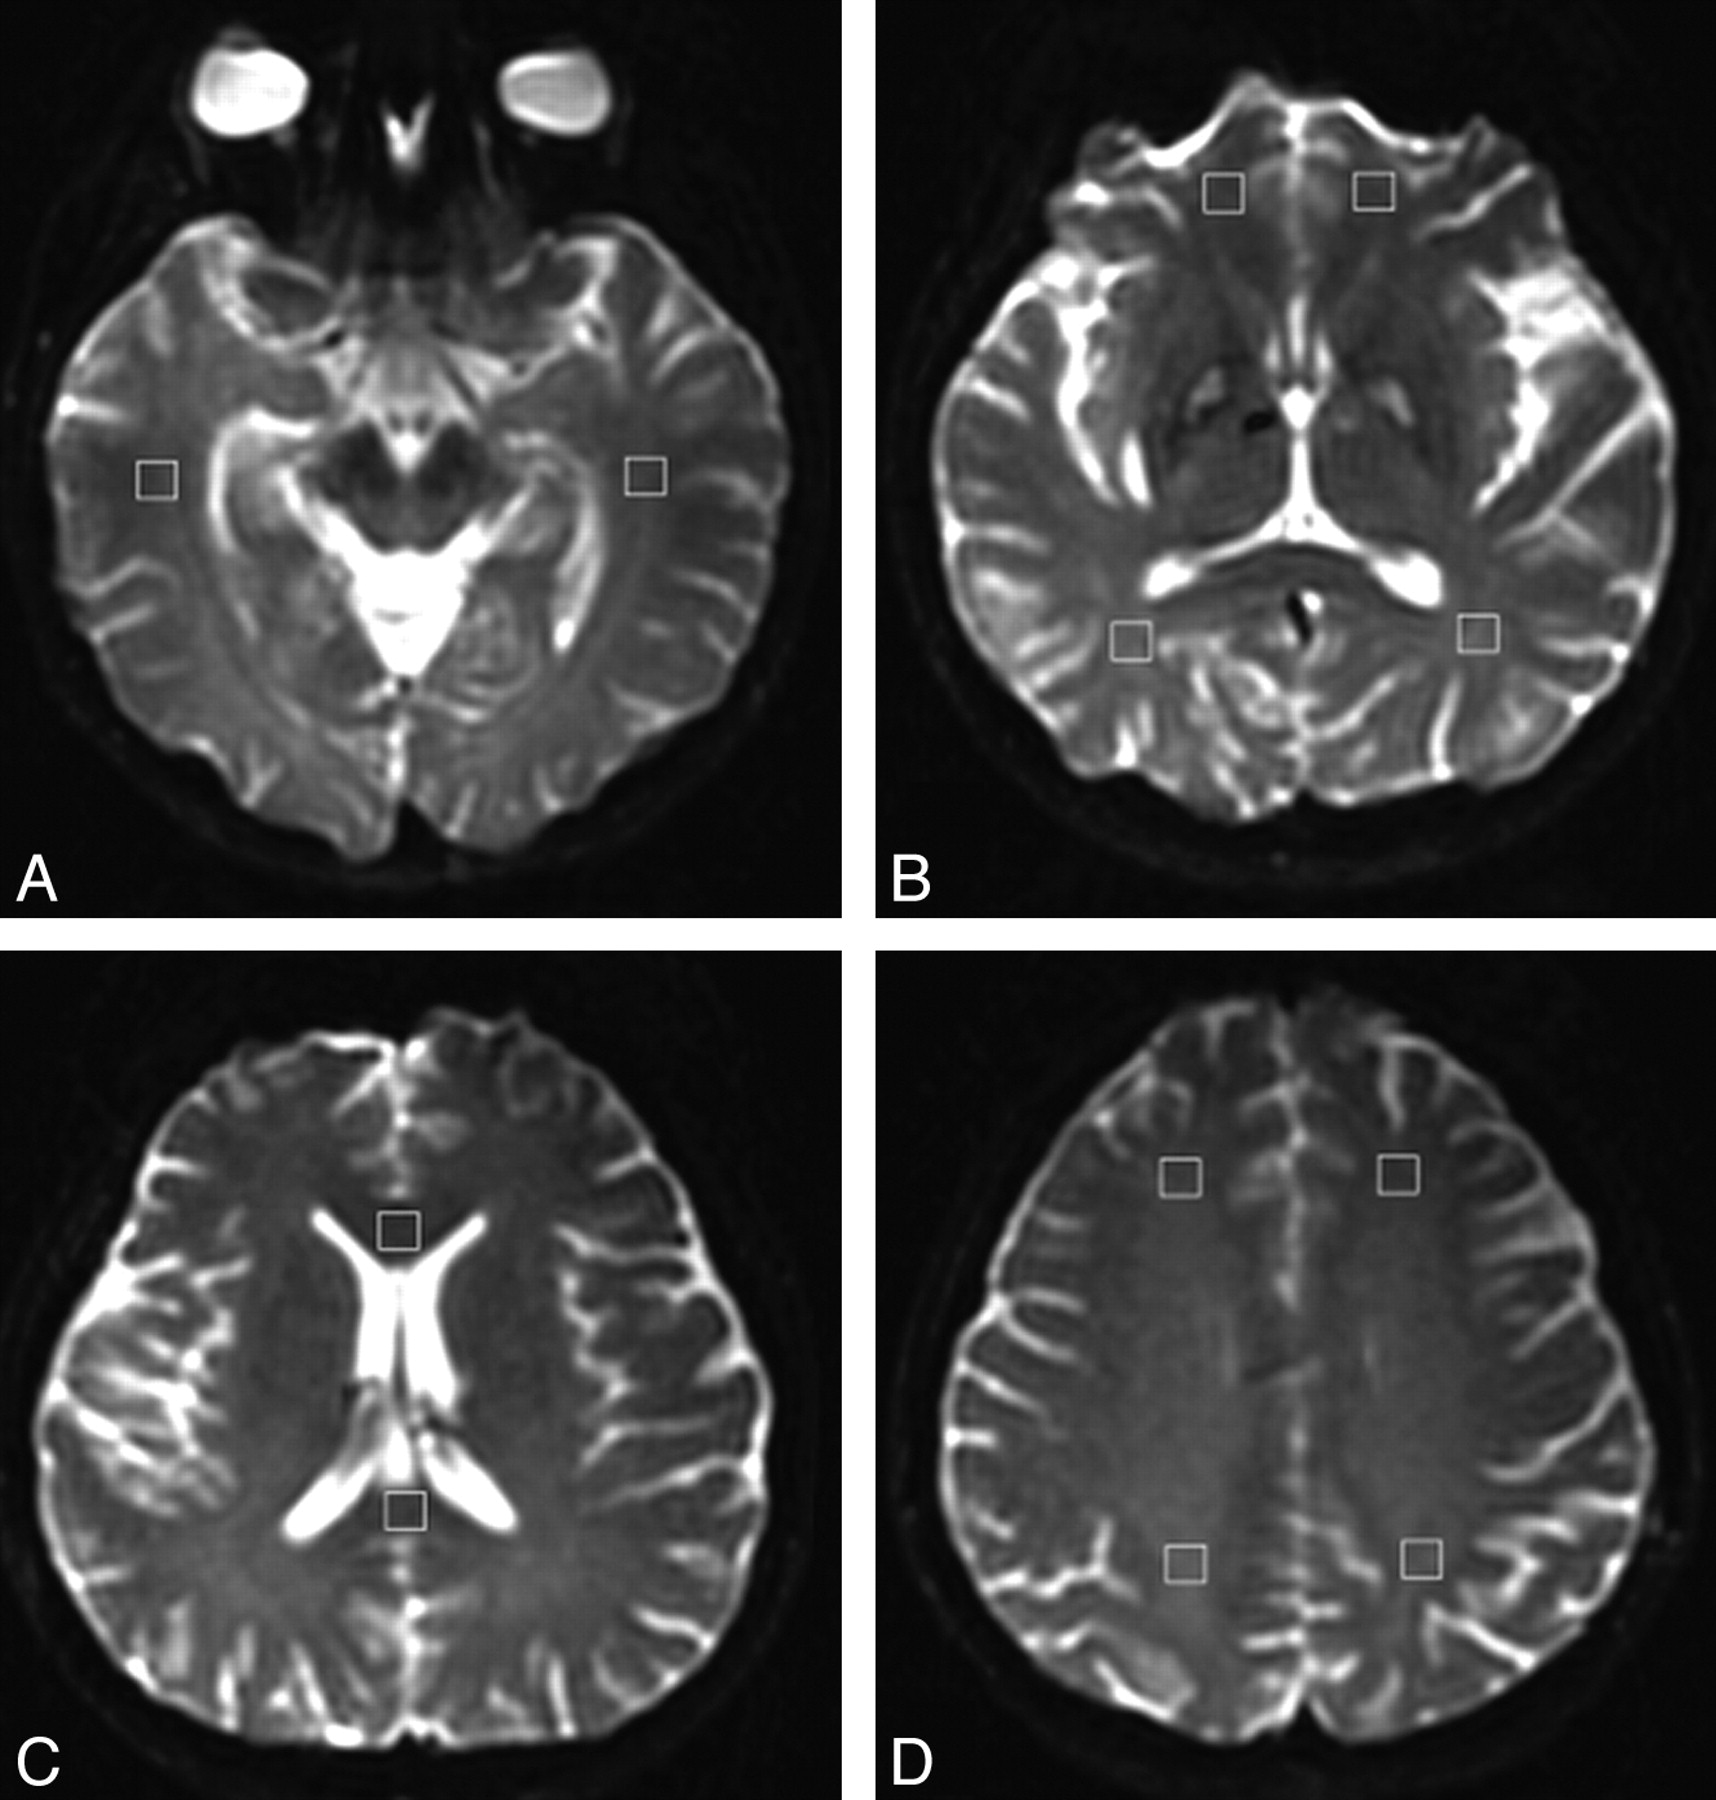

Regions of interest, 50–100 mm2 depending on the anatomic region, were measured by 1 radiologist and confirmed by another radiologist to avoid malpositioning (Fig 1). These measurements were performed according to the method described by Bozzali et al.24 Regions of interest were placed on the genu and the splenium of the corpus callosum, the anterior and the posterior limbs of the internal capsule, and the WM of the subcortico-orbitofrontal, high frontal, parietal, occipital, and temporal regions. For temporal lobe WM, we sampled 2 contiguous sections. Regions of interest were placed lateral to the temporal horn of the lateral ventricle (Fig 1A). The anterior internal capsule (bounded by the head of the caudate nucleus and the globus pallidus) and the posterior internal capsules (defined by the globus pallidus and the thalamus) were measured on 2 contiguous sections. In the orbitofrontal WM, regions of interest were bilaterally placed on the most caudal section of the lateral ventricles. Occipital lobe regions of interest were placed in the optic radiations of 2 contiguous sections, starting from the most caudal section on which the occipital horn of the lateral ventricle was imaged (Fig 1B). Regions of interest at the genu and splenium of the corpus callosum were placed on 3 consecutive sections on which they were fully volumed (Fig 1C). Regions of interest at the high frontal and parietal lobes were positioned in the WM, anterior and posterior to the central sulcus on the most caudal section on which they were visible and on the subsequent cranial section (Fig 1D).

Location of the WM regions of interest in a patient with CO intoxication. A, WM of temporal lobes. B, WM of orbitofrontal, occipital, anterior, and posterior limbs of the internal capsule. C, Genu and splenium of the corpus callosum. D, WM of the frontal and parietal lobes.